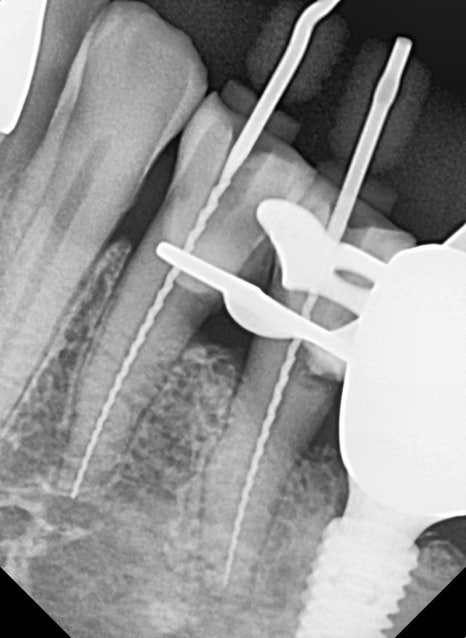

250321

1년 반이라는 시간이 꽤 길었던 건지

이미 충치가 많이 커진 상태였어요.

1년 반 전 엑스레이 사진과 그 후 사진입니다.

충치 크기 차이가 꽤 많이 나죠?

이미 신경까지 침범한 충치로 인해

신경치료를 결정할 수밖에 없었습니다.

250321~250421

뿌리 신경의 길이를 끝까지 재서 소독하는 과정을 2~3번 거친 후 신경치료를 끝냈습니다.